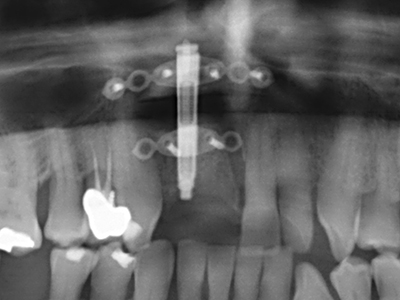

La preparación de la ventana lateral en la elevación del suelo del seno maxilar representa un enorme reto, sobre todo para profesionales de la implantalogía que tienen poca experiencia en técnicas quirúrgicas. Retirar la cobertura ósea del seno maxilar sin provocar daños en la membrana de Schneider es tan solo una parte de la operación; tras crear un acceso suficiente, es preciso movilizar con cuidado la mucosa del seno maxilar a fin de dejar espacio para el material o los implantes que vayan a incorporarse. En esta aplicación la cirugía piezoeléctrica resulta útil en dos sentidos: por un lado, el uso de insertos diamantados permite realizar una retirada selectiva del hueso y, si se actúa con cuidado, la membrana permanece intacta, y por otro lado, las frecuencias de ultrasonidos favorecen también un desprendimiento sin problemas de la membrana, pues se transfieren al espacio comprendido entre la mucosa y el suelo del seno maxilar gracias al uso de piezas romas especiales (Cassetta, Ricci et al. 2012, Pereira, Gealh et al. 2014) (Rickert, Vissink et al. 2013). De este modo, no es de extrañar los trabajos publicados en la actualidad sobre la técnica de elevación del suelo del seno maxilar mediante la técnica de Caldwell-Luc con instrumentos piezoeléctricos (Wallace, Tarnow et al. 2012).